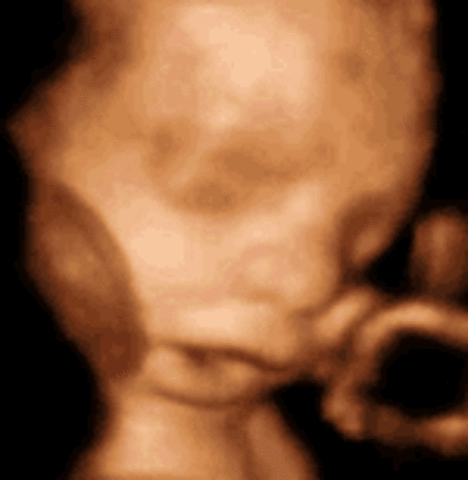

• Week 28

Week 28

Hair is visible through 4D ultrasounds. Milk teeth have started growing under the gums and eyes start to move.